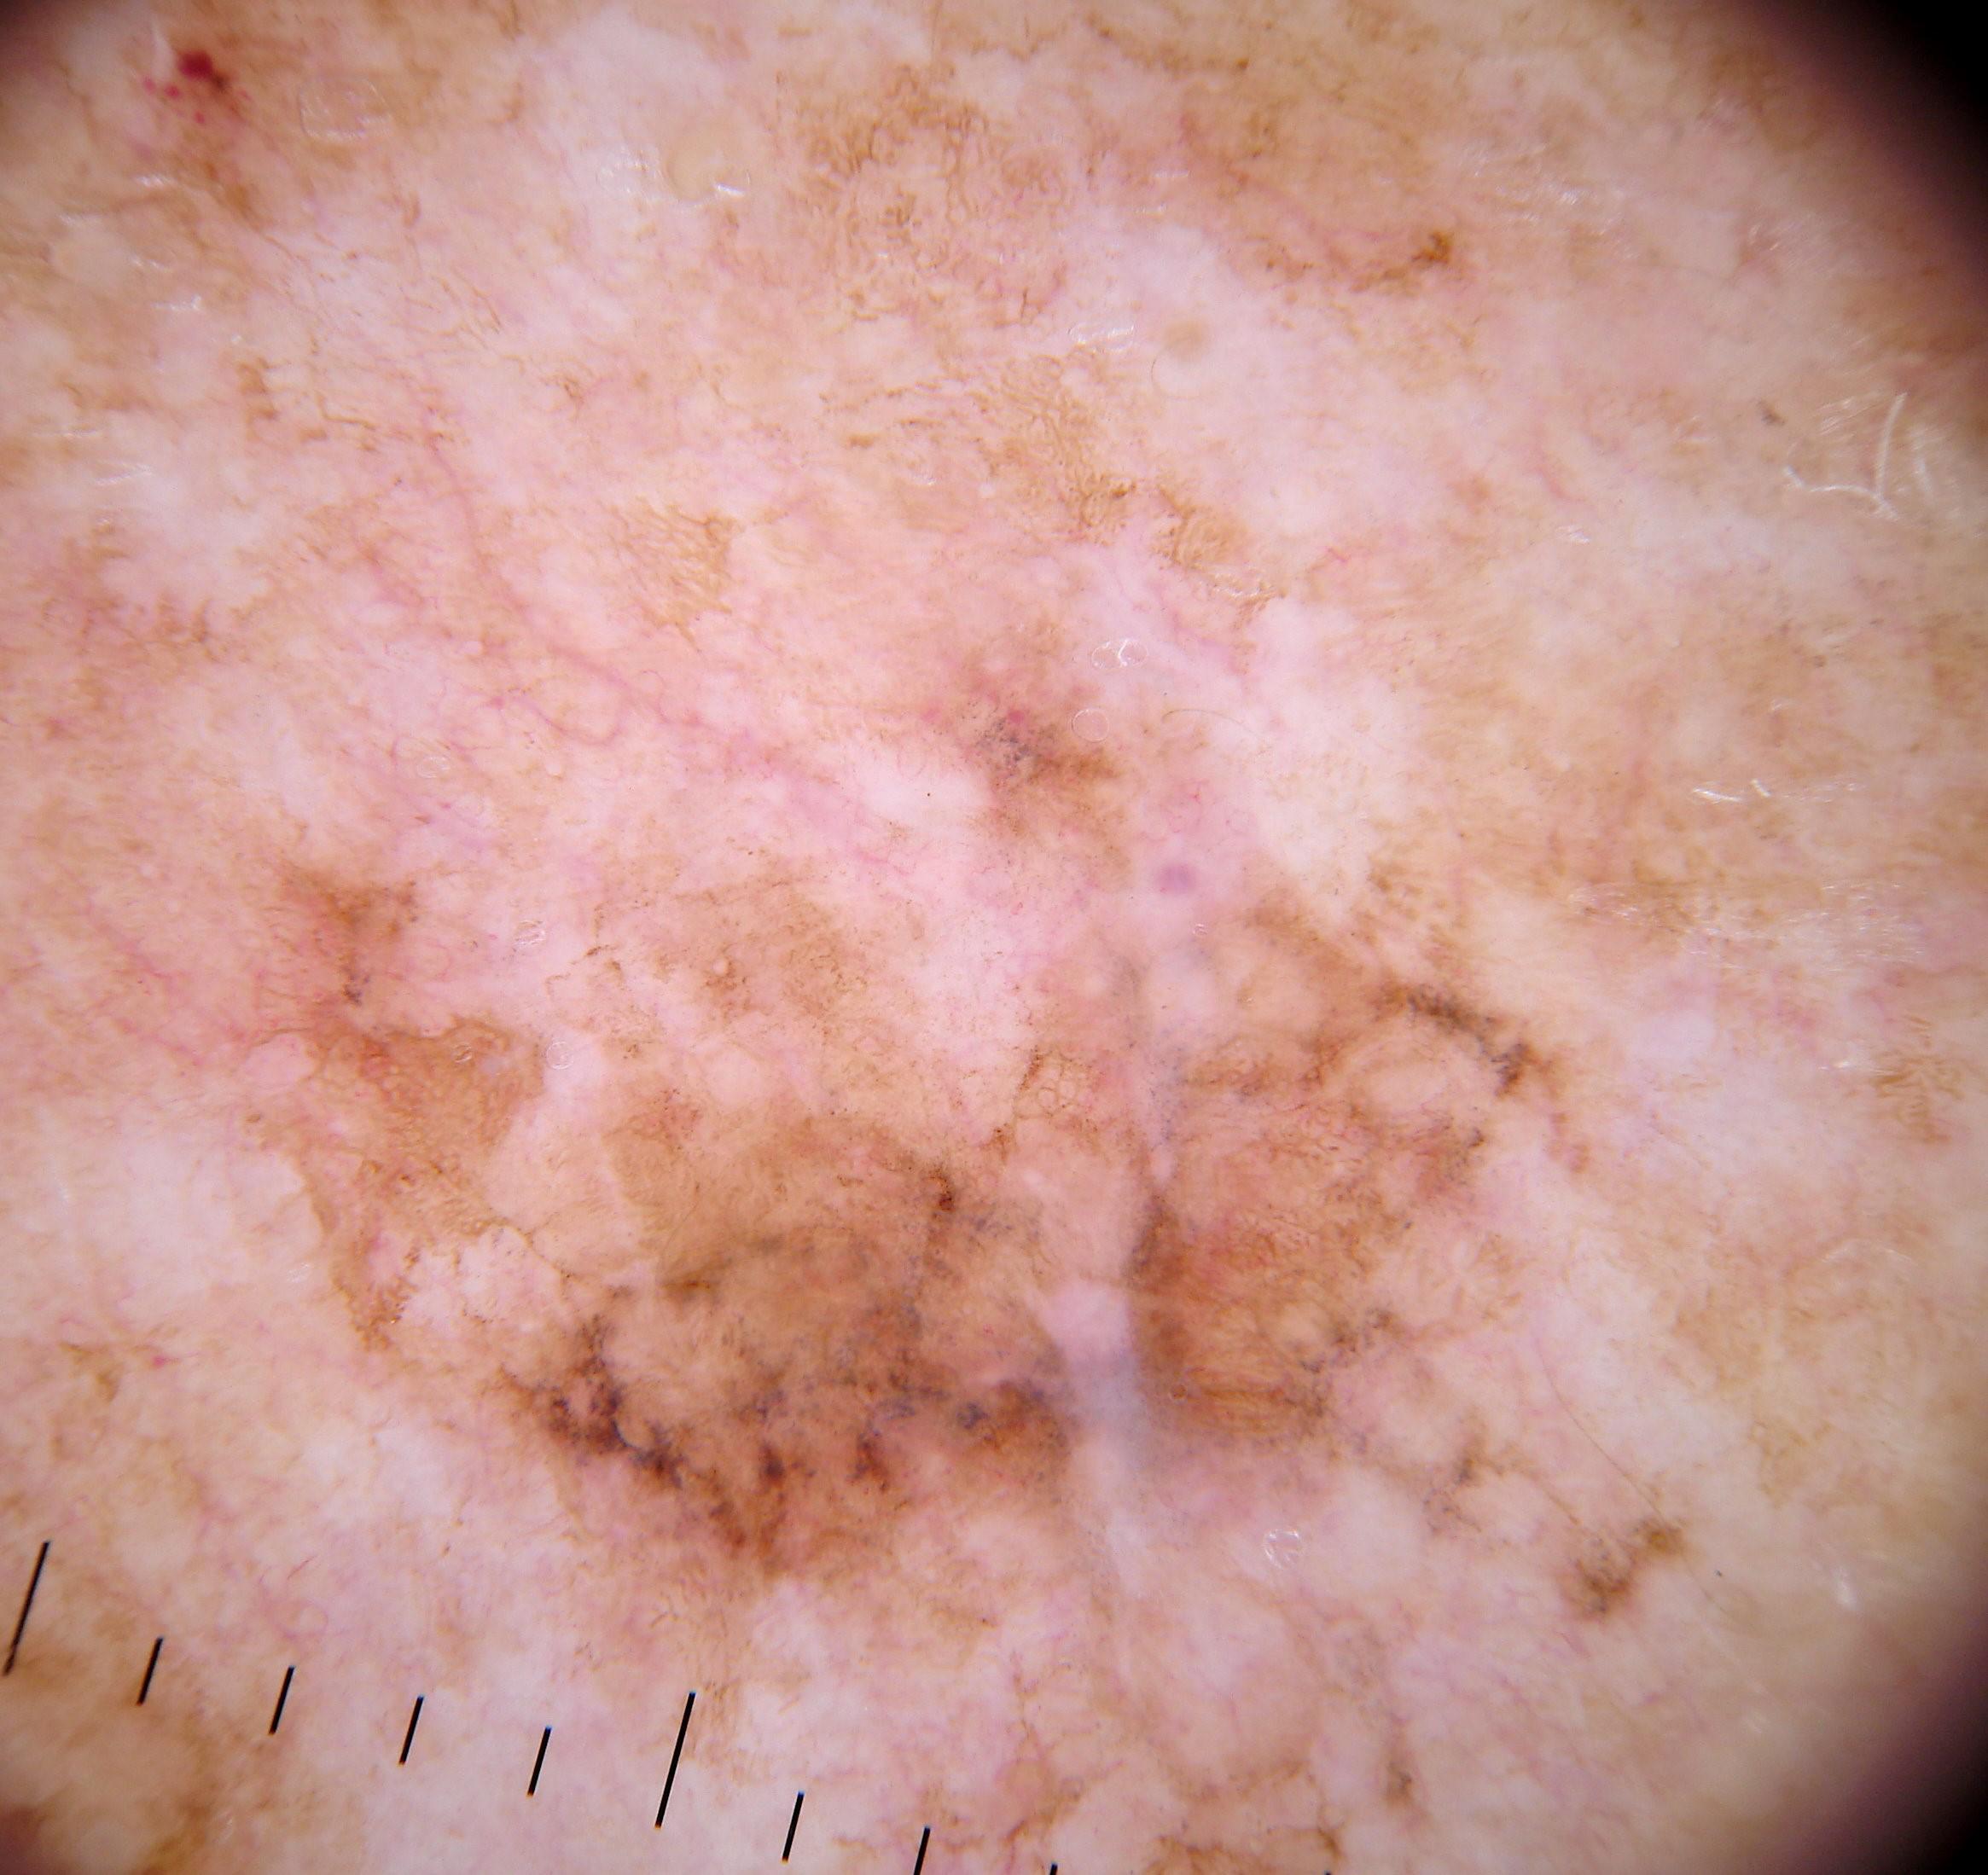

{

"age_approx": 80,

"anatom_site_general": "anterior torso",

"concomitant_biopsy": true,

"dermoscopic_type": "contact polarized",

"diagnosis_1": "Malignant",

"diagnosis_2": "Malignant melanocytic proliferations (Melanoma)",

"diagnosis_3": "Melanoma in situ",

"diagnosis_confirm_type": "histopathology",

"family_hx_mm": false,

"image_type": "dermoscopic",

"mel_thick_mm": "0.00",

"melanocytic": true,

"patient_id": "IP_4057359",

"personal_hx_mm": false,

"sex": "male"

}